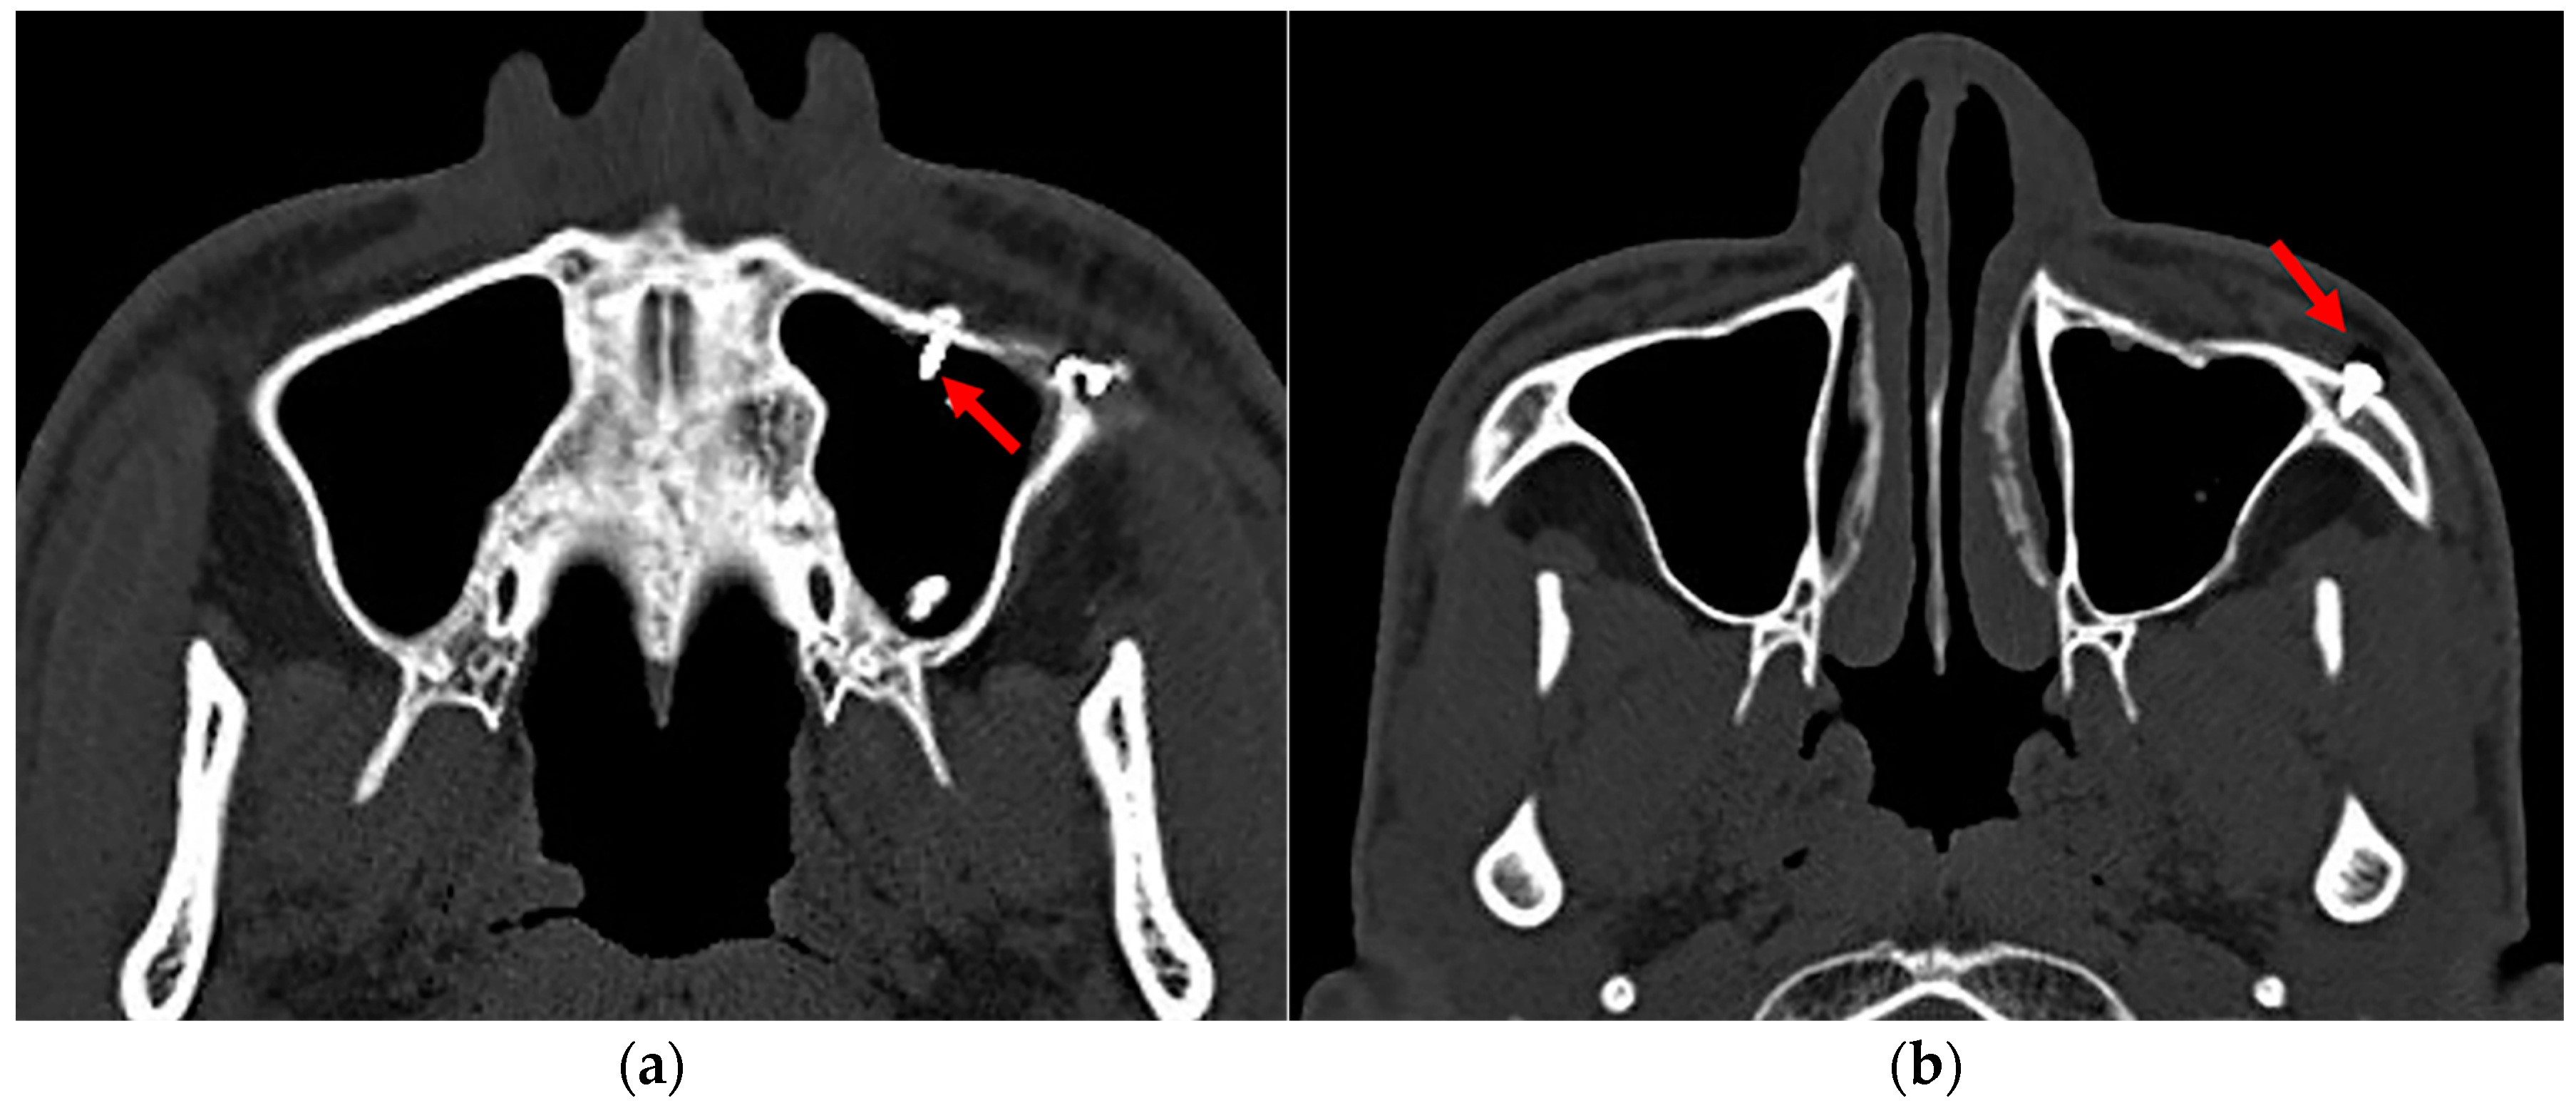

| Number of screws implanted in the maxillary sinus (X7) | |

| Number of screws penetrating the maxillary sinus (X8) | |